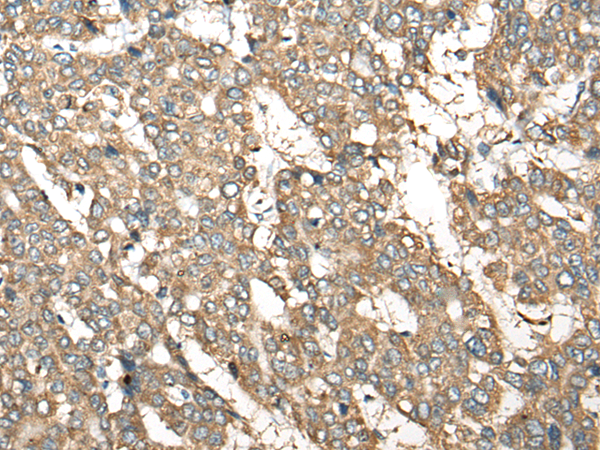

分类: 科研抗体货号: P13129别名: AMID; PRG3应用: IHC反应种属: Human, Mouse